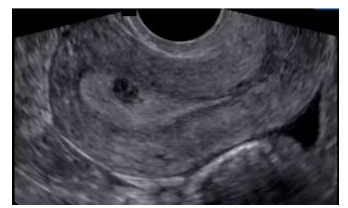

O mioma (leiomioma) uterino é um tumor benigno, muito comum, que pode acometer até 70% das mulheres com 50 anos de idade. Para sistematizar a descrição dos miomas, foi criada a classificação da FIGO (Federação Internacional de Ginecologia e Obstetrícia) juntamente com o grupo MUSA (Morphological Uterus Sonografic Assessment), utilizando estes parâmetros classifique o nódulo abaixo: